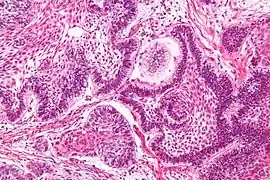

| Micrograph of an ameloblastoma showing the characteristic palisading and stellate reticulum. H&E stain. | |

Conventional ameloblastomas have both cystic and solid neoplastic structures.

Solid structure

Solid areas contain fibrous tissue islands or epithelium that interconnect through strands and sheets. The epithelial cells tend to move the nucleus away from the basement membrane to the opposite pole of the cell. This process is called reverse polarization. Two main histological patterns most often occur: follicular and plexiform. Other less common histological variants include acanthomatous, basal cell, and granular cell patterns.[8]

Follicular

The most common follicular type has an outer arrangement of columnar or palisaded ameloblasts-like cells and inner zone of triangular shaped cells resembling stellate reticulum from the bell stage of tooth development.[8]